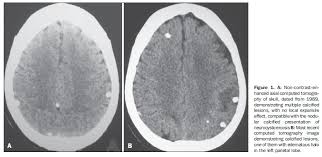

An Ambispective Cohort Study To Assess Seizure Recurrences In Children With Calcified Parenchymal Neurocysticercosis In The American Journal Of Tropical Medicine And Hygiene Volume 101 Issue 4 2019